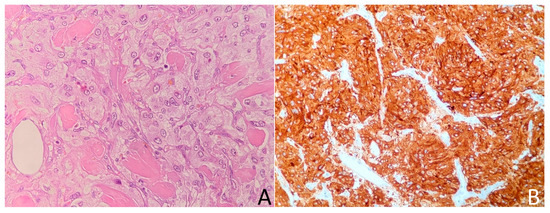

2.1. Case 1

2.2. Case 2

2.3. Case 3

2.4. Case 4

2.5. Case 5

2.6. Case 6

2.7. Case 7